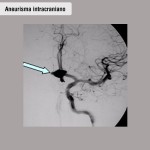

Foto